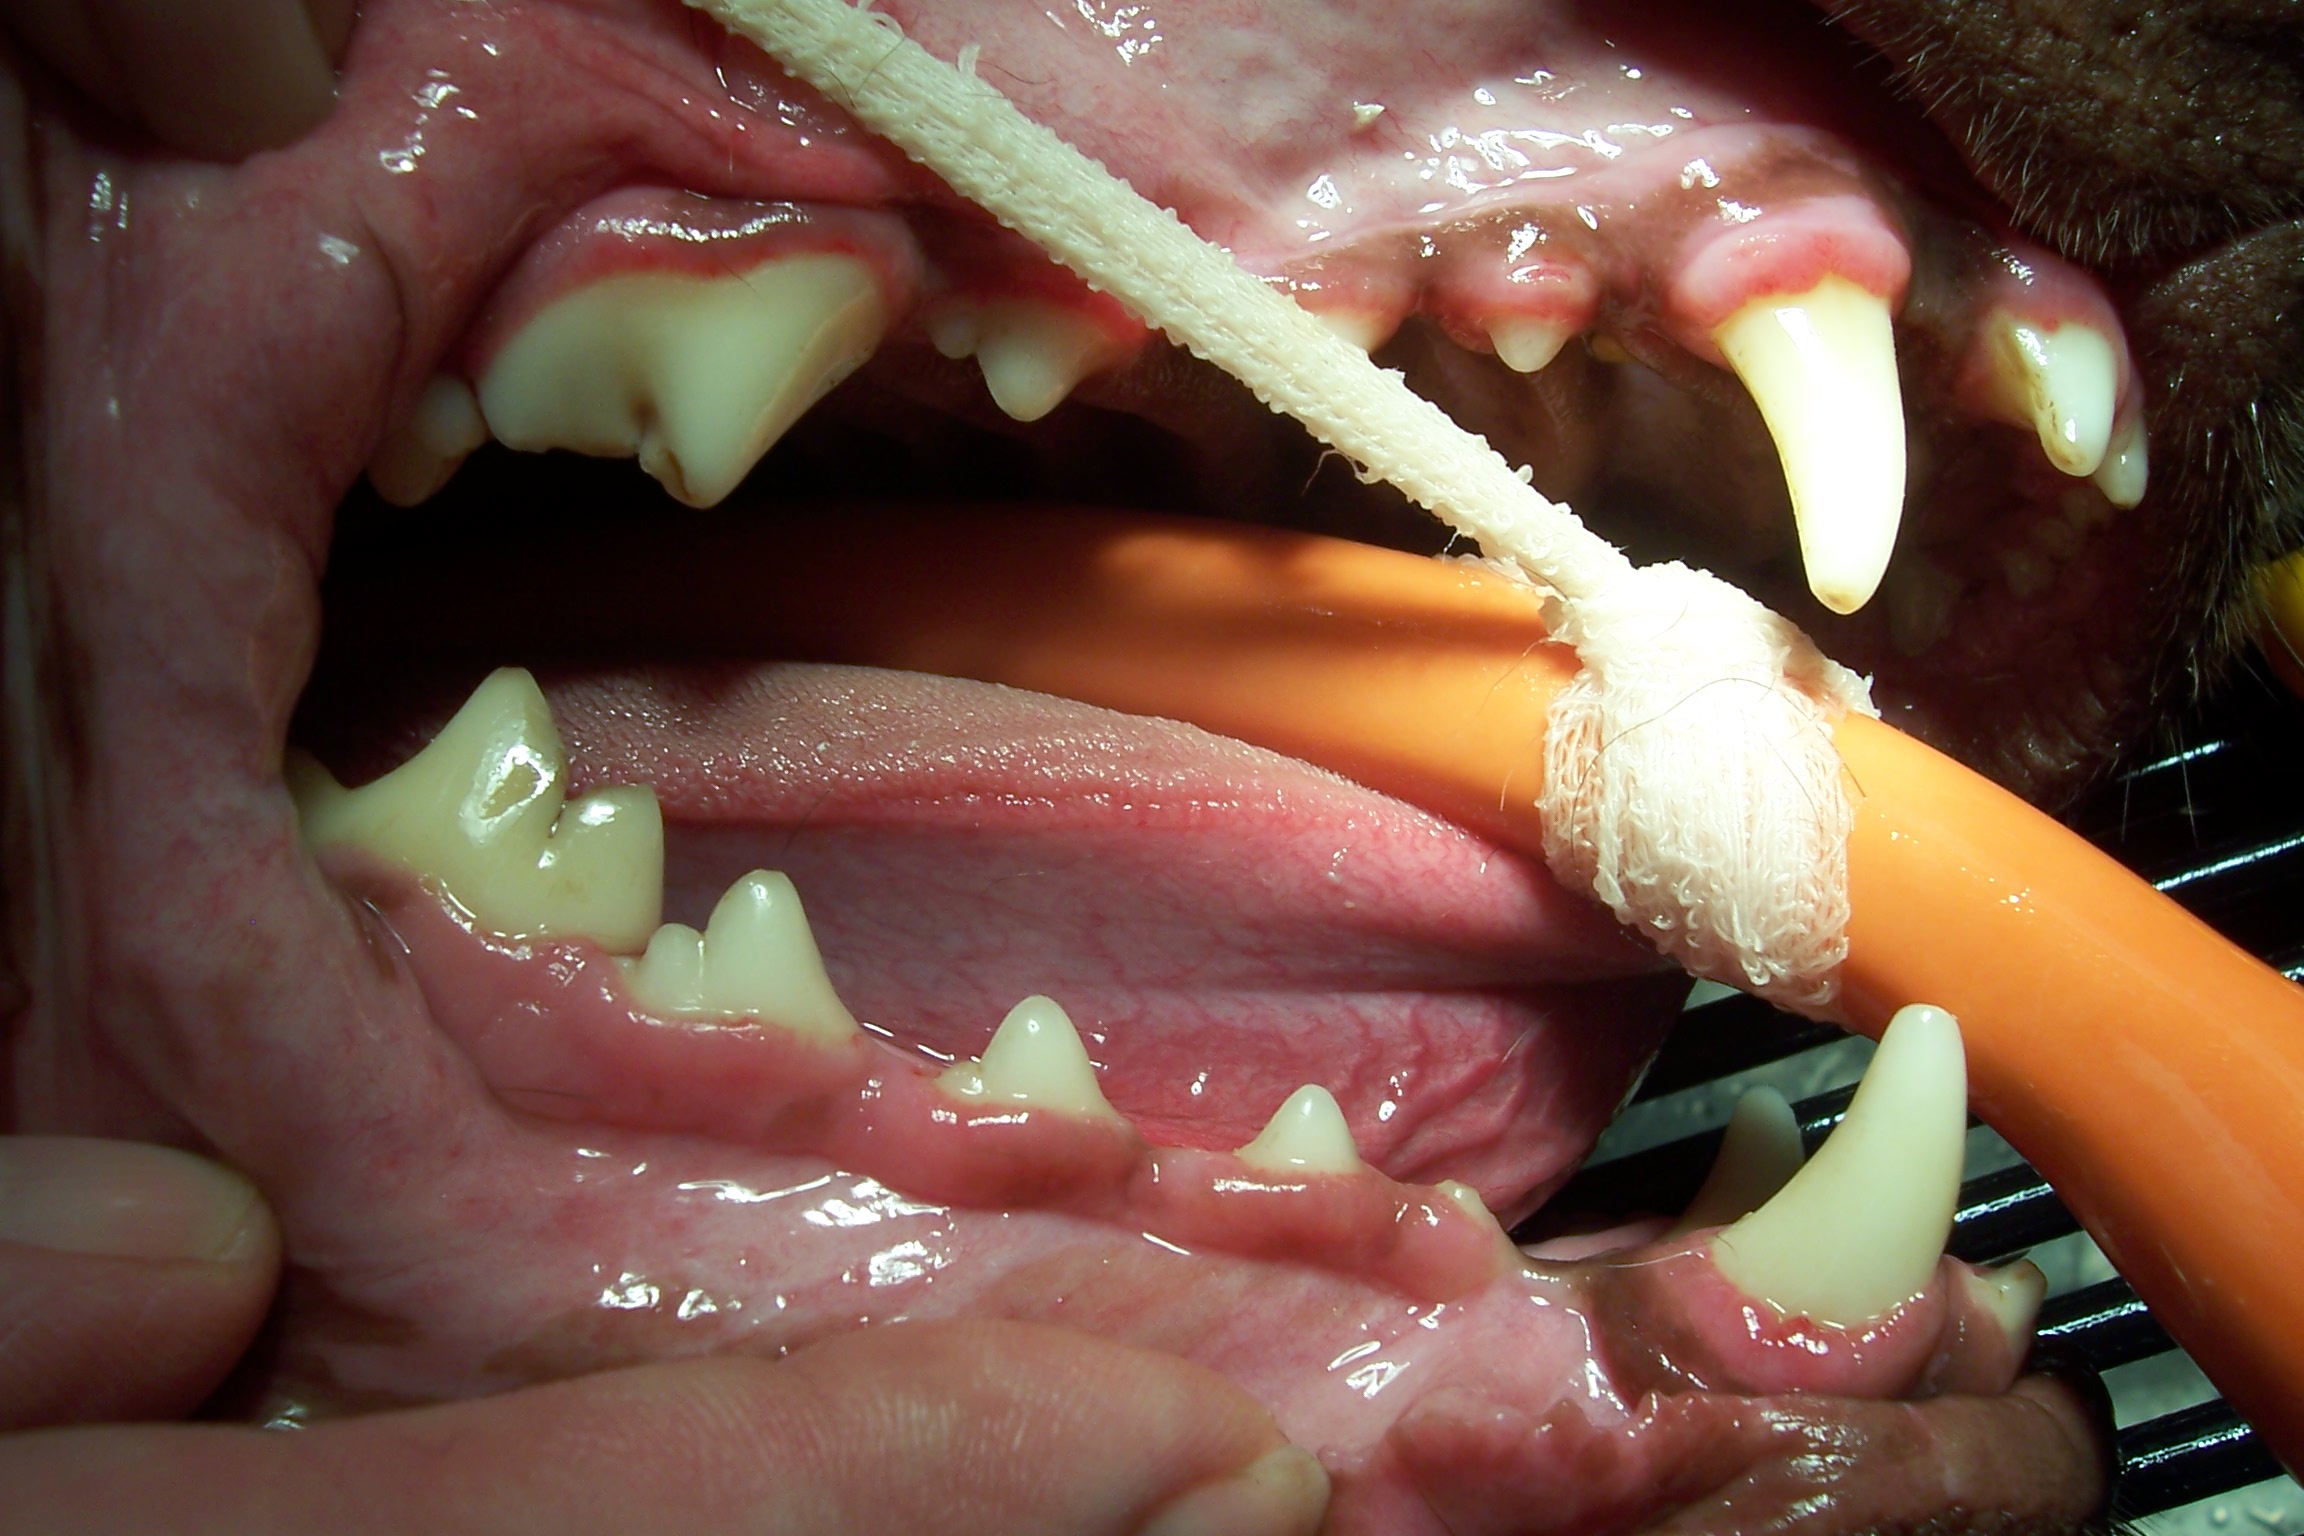

Mouth before dental cleaning

-